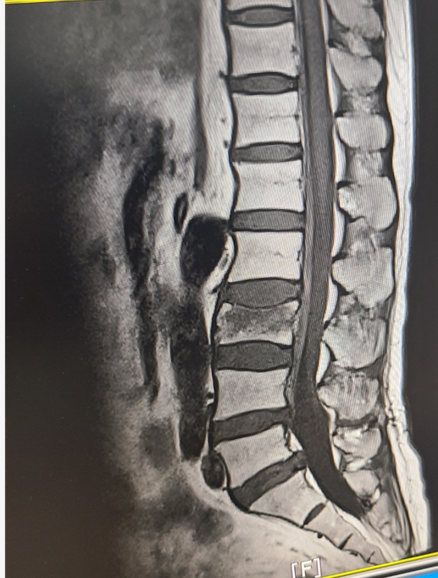

🔹 요추 3번 척추 압박골절 진단과 수술을 하지 않은 이유

본 이미지는 보호자의 개인 기록용 참고 자료입니다.

의료 정보 제공이나 진단 목적의 이미지가 아니며, 정확한 판단은 반드시 전문의 상담이 필요합니다.

정밀 검사와 MRI 촬영 결과, 다행히 기존에 수술했던 디스크 부위는 문제가 없었습니다. 하지만 요추 3번(척추 3번) 압박골절이라는 진단을 받게 되었습니다. 원장님 설명에 따르면, 엄마는 허리디스크로 인한 다리 힘 저하뿐만 아니라 골밀도 수치가 매우 낮은 상태였다고 합니다. 젊은 사람이라면 가벼운 타박상으로 끝날 일이었지만, 골다공증이 있는 상태에서는 작은 충격도 뼈가 으스러지는 압박골절로 이어지기 쉽다는 것이었죠. 엄마는 50대 후반으로 아주 고령은 아니셨기에, 원장님께서는 바로 수술(골시멘트 등)을 하기보다 보존적 치료를 권하셨습니다. 2주 정도 절대 안정을 취하며 뼈가 붙는 양상을 지켜보고, 만약 경과가 좋지 않으면 그때 수술을 고려하자는 조언을 들었습니다.